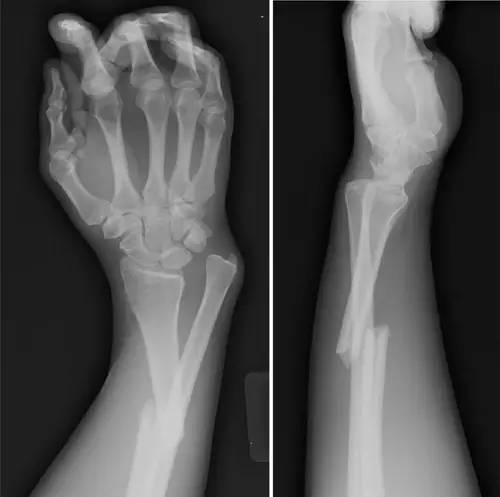

2. Colles 骨折

桡骨远端骨折,伴有桡骨远端向背侧的移位,可以有或没有尺骨干的骨折。具有这几个特征:背侧粉碎、向背侧成角、向背侧移位且挠骨短缩的关节外骨折。

典型 colles 骨折,枪刺样、餐叉样畸形